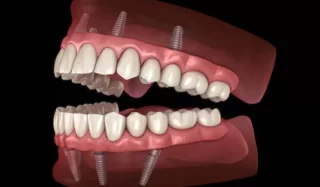

Az all-on-four, all-on-six technika lehetővé teszi egy teljesen fogatlan páciens számára is, hogy akár egy napon belül fogimplantátumon rögzített, teljesen stabil fogsorra cserélje korábbi kivehető protézisét.

A legtöbb esetben megoldást nyújt azoknak is, akiket korábban eltanácsoltak a fogimplantátumos beavatkozásoktól az előrehaladott csontleépülés miatt. Így ők is viszonylag csekély műtéti beavatkozás révén nyerhetik vissza magabiztos mosolyukat és teljes rágóképességüket. Bizonyos esetekben szükség lehet egyidejű, kiegészítő csontpótlásra is, kizárólag CT vizsgálatot követően lehet pontos tervet készíteni, a fogimplantátum beavatkozásokat elkezdeni.

Az eljárás lényege, hogy egy forradalmi újításként az állcsontok elülső, úgynevezett tömör csontos régiójába kerül beültetésre alul minimum 4, illetve felül minimálisan 6 darab fogimplantátum oly módon, hogy a hátsók egy bizonyos ferde szögben rögzülnek. Az esetek túlnyomó többségében még idős korban is található alkalmas terület a front régióban e beavatkozás elvégzésére. A fogimplantátumokhoz legtöbbször csavarozható módon tudjuk rögzíteni az új, teljesen fix fogsorokat, így akár egy napon belül a korábbi kivehető protézisek helyére esztétikus, funkcióstabil rögzített fogsor kerül. A fogsor rögzítésére szolgáló fogimplantátum beültetése esetén a gyógyulási idő 3-6 hónap, melynek leteltével van lehetőség a végleges, akár a legmagasabb esztétikájú cirkónium körhidak elkészítésére, a teljes fogsor rögzítésére.